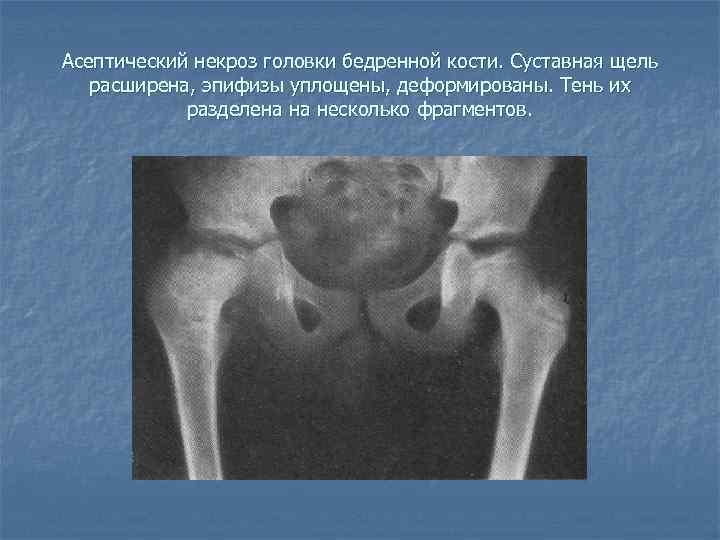

Диагностика ТБС рентгеном и асептический некроз: особенности лечения

Раздел: Снимки-откровения